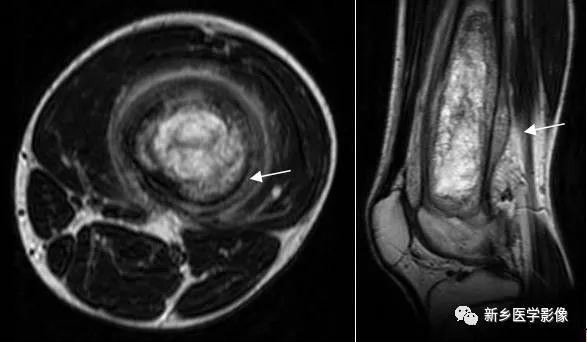

骨质破坏MRI图像

股骨中下段MRI T1WI矢状面(a)、T2WI冠状面(b)和T2WI矢状面脂肪抑制(c)图像示股骨下段髓腔内多发不规则异常信号(相对于骨髓),软组织肿块,为骨肉瘤。